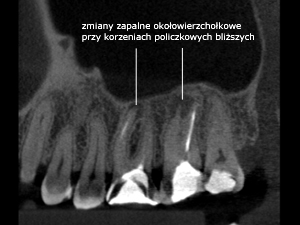

Pacjent lat 37 leczył się laryngologicznie z powodu bóli głowy i podejrzenia stanu zapalnego zatok szczękowych. Został również skierowany na badanie stomatologiczne celem wykluczenia ognisk zapalnych zębopochodnych. Badanie RVG wykazało iż zęby 26 i 27 (szóstka i siódemka górna lewa) miały wypełnione trzy kanały korzeniowe (kilka lat temu). Ze względu na nawracające dolegliwości bólowe głowy zalecono dodatkowo diagnostykę przestrzenną 3D przy pomocy tomografii wolumetrycznej. Badanie wykazało istnienie dużej zmiany zapalnej wokół korzeni policzkowych bliższych oraz obecność dodatkowych kanałów korzeniowych, które nie były uprzednio znalezione i oczyszczone w trakcie konwencjonalnego leczenia kanałowego. Wykonano leczenie kanałowe zęba 27 w czasie którego odszukano, oczyszczono i wypełniono 5 kanałów korzeniowych. Dolegliwości bólowe wyciszyły się po około 2 tygodniach i do chwili obecnej brak jest nawrotów bólu głowy.